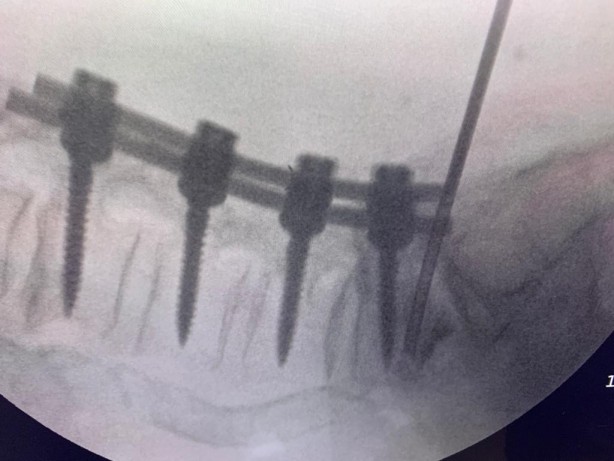

Beyin ve Sinir Cerrahisi Uzmanı Prof. Dr. Kemal Yücesoy, vidalı omurganın kırığına dünyada ilk kez transforaminal transdiskal yaklaşımla sement desteği yaptı. Geliştirdiği yöntem, nöroşirürji alanında dünyanın en prestijli dergilerinden olan World Neurosurgery'nin son sayısında yayımlanarak literatüre girdi. Hastaların sadece 5 dakikasını alan ve 2 saat sonra günlük hayatına dönmesini sağlayan yöntem, Türkiye’ye gurur yaşattı.

Uzun süre, vidayı çıkarmadan kemik çimentosunu koyma konusunda çalışmalar yaptığını belirten Prof. Dr. Yücesoy, “Kapalı bel fıtığı ameliyatlarında iğneyle sinirin altına girerek izlediğimiz bir yol var. ‘Hastaların kemiğinin içine bu yoldan girilebilir’ diye düşündüm ve bunu da uygulamaya başladım. Bu yöntemde, hastaya lokal anestezi uyguluyoruz. Kıkırdağın olduğu bölümden diskin içine iğneyle girip oradan da kemiğin içine ulaşıyoruz ve çimentoyu koyuyoruz. Bu daha önce hiç uygulanmamış bir yol. Kırılmış vidalı bir kemiğe ilk kez o vidayı çıkarmadan kapalı yöntemle girip müdahale etmiş olduk” diye konuştu.

Her yıl binlerce hastanın vidalı ameliyat olduğunu hatırlatan Yücesoy, “Çarpma, düşme, kemikte çökmeler olduğunda özellikle ileri yaş hastalarda bu durum risk oluşturuyor. Böyle bir hasta grubu karşımıza çıktığında elimizde bu alternatifin olması çok önemli. İşlem 5 dakika sürüyor ve hasta 2 saat sonra evine gidiyor. Hastalar hayatlarından gayet memnun. Hastalar tabii ki en az yükle rahatsızlığından kurtulmak istiyor. Dolayısıyla onların da bu yöntemle hayatı kolaylaşmış oluyor. Bunu diş dolgusu gibi düşünebilirsiniz. Dişinize dolgu yaptırıp 2 saate nasıl normal hayata devam ediyorsanız bu işlemde de 2 saat sonra normal hayata devam ediyorsunuz” ifadelerini kullandı.